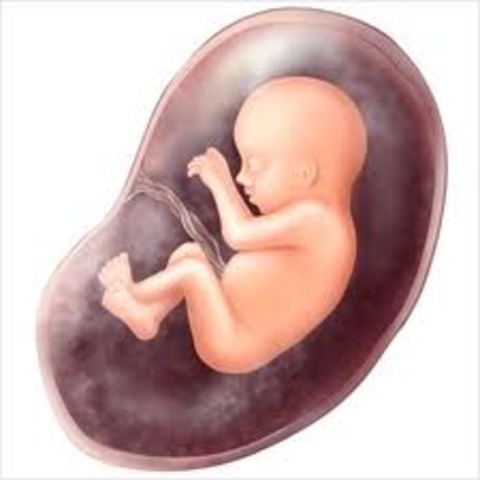

• week 12

week 12

The fetus is now about 2.5 inches (6cm) length and weighs about 0.7 ounce (20 g).

The feet are almost half an inch (1cm) long.

The fetus starts moving spontaneously.

The face is beginning to look like a baby's face.

The pancreas is functioning and producing insulin.

Fingernails and toenails appear.

The baby can suck his thumb, and get hiccups.